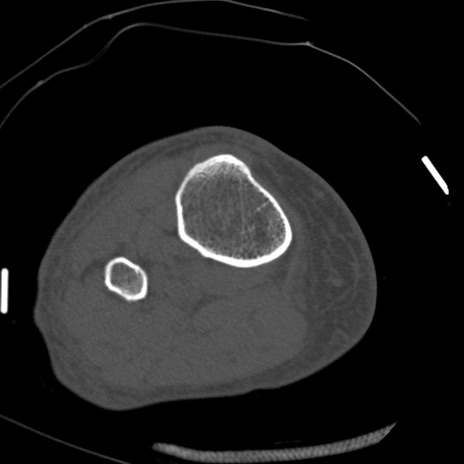

症例28 右膝関節CT(横断像)

右膝関節CT